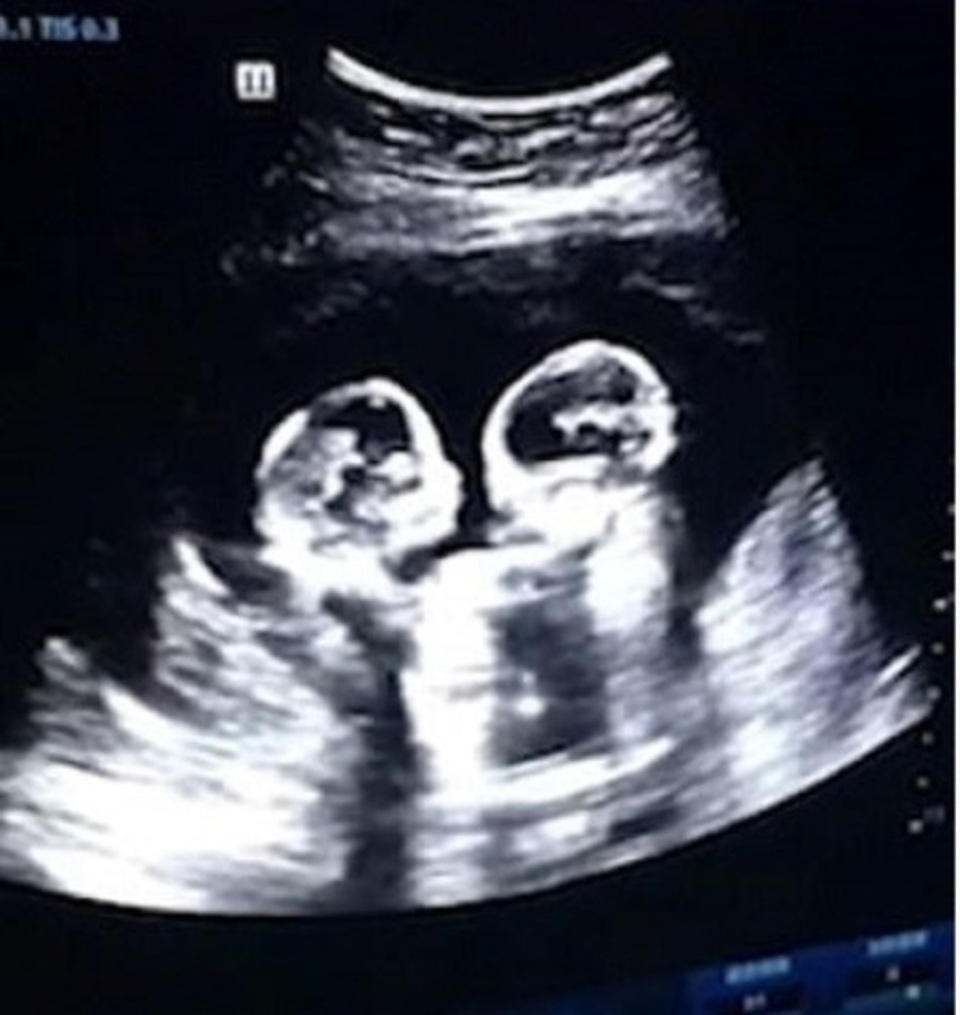

(Dân trí) - Hai chị em sinh đôi Tao Yimo và Tao Yi’an đã trở nên nổi tiếng khắp truyền thông xã hội Trung Quốc ngay từ thời vẫn còn nằm trong bụng mẹ. Nguyên nhân bắt nguồn từ một video siêu âm thai nhi của người mẹ, cho thấy cặp sinh đôi này có “hành vi ẩu đả” rõ ràng.

Mẹ của hai đứa trẻ là Wang Lu, 26 tuổi, đã mang thai được 18 tuần khi tiến hành siêu âm. Báo MailOnline cho biết đoạn siêu âm được quay lại vào cuối năm ngoái, trong quá trình kiểm tra trước khi sinh của Wang Lu.

Đoạn video dài 30 giây cho thấy cảnh hai bé dùng cả tay lẫn chân đánh nhau trong bụng mẹ đã gây sốt trên ứng dụng chia sẻ video Douyin. Tuy nhiên, hóa ra hai bé gái đã phải giao tranh với nhau vì là một cặp sinh đôi Momo (cặp song sinh đơn bào đơn sắc) hiếm hoi. Đây là một tình trạng mang thai với nguy cơ rủi ro vô cùng cao khi hai đứa trẻ có chung túi ối và nhau thai bên trong bụng mẹ.